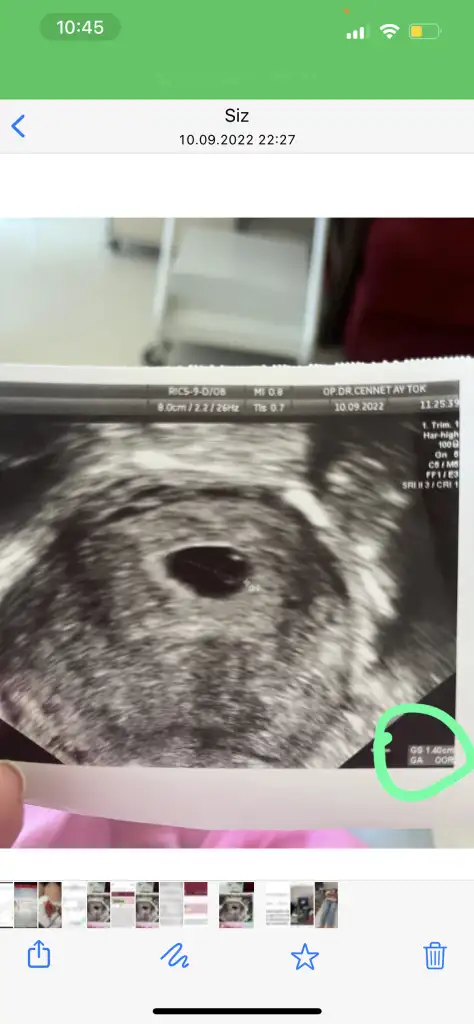

Kızlar yolk kesesinin altında sanki c şeklinde bebek ben görüyorum gibi🙈 doktor görmemiş olamaz di mi kendimi kandırıyorum sanki🙈🥹

Eklentiler

• 3A715E75-9D57-46EE-B36E-D9E0C4A1D876.webp

3A715E75-9D57-46EE-B36E-D9E0C4A1D876.webp

21,8 KB · Görüntüleme: 72

Aslında dikkatli bakınca bana da bebek var gibi geldi yolk kesesinin orda ama tabi çok da anlamıyoruz. Sonuçta doktor gözden kaçırmazdı herhalde. Ama bence senin bebeğin görünecek hiç merak etme